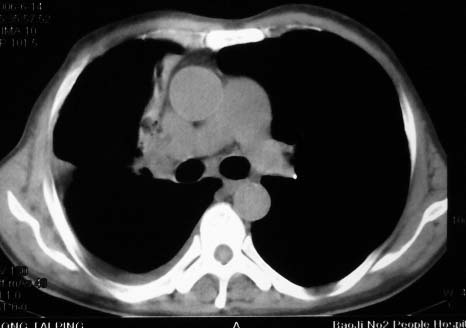

病史:男,64岁,咳血,咳痰,发热3天,wbc---1.2万

影象表现:右肺上叶大片状、网格状及索条致密影,蜂窝影,其内参杂斑点状小结节,密度不均匀,内见含气支气管像,纵隔内见肿大淋巴结.

抗炎10天后无好转出现胸水,考虑:肺结核合并间质纤维化

抗感染病变无明显改善,右上叶大片状增弥不均匀病灶,夹杂网状及支气管充气像,肺门纵隔淋巴结肿大,右侧胸腔积液。考虑1混合感染伴肺间质改变[警惕特殊感染,如真菌]。2细支气管肺泡癌。建议结合临床及进一步检查[如痰,胸水脱落细胞检查及支气管镜检灌洗或穿刺活检

右肺上叶见大片状及索条致密影,密度不均,内见含气支气管症,纵隔内见肿大淋巴结.

影象表现:右肺上叶大片状、网格状及索条致密影,蜂窝影,其内参杂斑点状小结节,密度不均匀,内见枯枝样含气支气管像,纵隔内见肿大淋巴结.胸膜广泛增厚,前胸壁似受累.少量胸腔积液.纵隔内淋巴结的直径>1.5cm.右侧胸廓体积缩小.考虑:1 肺结核合并间质纤维化 2 细支气管肺泡癌

右肺上叶大片状、网格状及索条致密影,蜂窝影,其内参杂斑点状小结节,密度不均匀,内见枯枝样含气支气管像,纵隔内见肿大淋巴结.胸膜广泛增厚,前胸壁受累增厚.少量胸腔积液.纵隔内淋巴结的直径>1.5cm.右侧胸廓体积缩小.考虑: 细支气管肺泡癌并肺内癌性淋巴管炎。